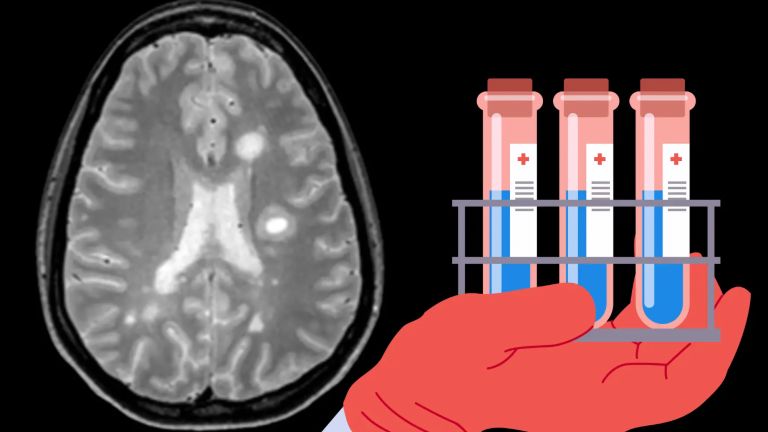

Think Consciousness Diseases Alzheimer's disease Percieve Hearing Percieve Vision Current Topic: Successful Aging What is going right in the brains of superagers? Successful Aging Diseases Successful aging The Old, Healthy Brain Some people seem to be unaffected by aging. Research is currently being conducted to find out why this is the case. Diseases Successful aging Molecular Detectives We are our memories. But neural firing alone cannot unravel the traces of memory. Diseases Successful aging The Secret of Neural Reserve From the hippocampus to the synapse: A research consortium is investigating which factors protect our thinking in old age Media video Diseases Successful aging Superagers: How can we age successfully? The brains of so-called “superagers” are 30 years younger than the age stated in their passports. Read the interview with researchers from SFB 1436 in Magdeburg. image Diseases Alzheimer's disease Media - Image | Graphic: The most important Milestones in Alzheimer's Research For more than 100 years, researchers have been searching for the causes of Alzheimer's disease. image Percieve Hearing Balance: The vestibular Labyrinth A labyrinth for balance: The vestibular system ensures equilibrium. image Percieve Hearing Hearing: Audio scale When does noise start to hurt? image Percieve Hearing Hearing: Types of Sound and their Perception Sometimes uniform, sometimes chaotic: the appearance of sound waves depends on their source. image Percieve Hearing Neural classics of linguistic competence Without Broca's area and Wernicke's area, we would be quite tongue-tied. image Percieve Hearing Hearing: The Cochlea The inner ear contains a spiral structure that is very important for hearing: the cochlea. image Percieve Hearing Hearing: Structure of the Organ of Corti Sound is converted into electrical impulses in the ear. The organ of Corti plays a crucial role in this process. News from the Institutes 26.02.2026 News from the Institutes New diagnostic markers for multiple sclerosis discovered in brain and spinal fluid Researchers at the MPI of Biochemistry and TUM have examined the cerebrospinal fluid of 5,000 patients with neurological diseases and discovered new diagnostic and prognostic markers for multiple sclerosis. 17.02.2026 News from the Institutes Unlearning Fear Faster Mice unlearn fear more quickly when certain brain cells are activated. This opens up new approaches to understanding anxiety disorders. 13.02.2026 News from the Institutes How the brain conquers space International research team reveals mechanisms of 3D vision 16.12.2025 News from the Institutes A human model of the blood-brain barrier Disruptions to the protective barrier contribute to the development of serious brain diseases such as stroke and Alzheimer's. 15.12.2025 News from the Institutes Combating loss of function in small vessels of the brain A new study identifies molecular factors that promote small vessel disease – and an active drug that can restore impaired vascular functions. 08.12.2025 News from the Institutes How Little Information Do We Need to Recognize a Face? Humans can spot familiar faces even in heavily blended images 04.12.2025 News from the Institutes Memory research: how respiration shapes remembering Respiration influences how the human brain processes stimuli and retrieves memories. 27.11.2025 News from the Institutes How a gene shapes the architecture of the human brain Organoids provide insights into brain development with unprecedented precision 26.11.2025 News from the Institutes When chimpanzees converse with each other Chimpanzee mothers interact with their young in a rhythmic way - almost like a human conversation 24.11.2025 News from the Institutes Why Do We Have a Consciousness? What is the evolutionary advantage of our consciousness? And what can we learn about this from observing birds? 21.11.2025 News from the Institutes Pigeons detect magnetic fields through their inner ear While many animals rely on the Earth’s magnetic field for orientation, how they detect and perceive magnetic stimuli is unknown. 06.11.2025 News from the Institutes Teamwork in the inner ear Our hearing is based on the organized grouping of proteins 05.11.2025 News from the Institutes Protective Brain Immune Cell State Discovered Discovery points to a potential new therapeutic pathway for Alzheimer’s disease 23.10.2025 News from the Institutes Guinea baboons share meat according to fixed social rules A study shows parallels between Guinea baboons and human hunter-gatherer societies 20.10.2025 News from the Institutes Controlling prostheses with the power of thought How research into movement planning in the brain is helping to advance the development of neuroprostheses 10.10.2025 News from the Institutes New Insights into the Molecular Basis of Ataxia Receptor responsible for stress-induced motor incoordination in people with ataxia identified. 01.10.2025 News from the Institutes Why women live longer than men Study traces the evolutionary roots of the lifespan gap between women and men 09.09.2025 News from the Institutes Signals from the brain reveal what color a person is seeing Success in predicting the color seen by an observer using the activity patterns measured in the visual cortex of other subjects 08.09.2025 News from the Institutes Structure of clusterin: a key protein against neurodegenerative diseases Crystallographic three-dimensional structure of human clusterin determined for the first time 01.09.2025 News from the Institutes Bremen Team Deciphers Information Processing Exact moment at which a signal hits receptive nerve cells determines how it is processed 28.08.2025 News from the Institutes What gives our brains their distinctive wrinkles? Study reveals how changes in cell behavior and numbers can drive the formation of distinctive grooves and ridges in the brain. 21.08.2025 News from the Institutes First mechanism for cognitive disorders in schizophrenia found Not only neurons, but also oligodendrocytes are essential 21.08.2025 News from the Institutes How flies sleep – and still manage to escape Charité study in Nature uncovers fundamental processes in the fly brain 15.08.2025 News from the Institutes Insights into Smelling Problems Associated with Alzheimer’s Tests of the sense of smell could help identify people who are developing Alzheimer’s at an earlier stage 15.08.2025 News from the Institutes Insights into Smelling Problems Associated with Alzheimer’s Tests of the sense of smell could help identify people who are developing Alzheimer’s at an earlier stage 13.08.2025 News from the Institutes New insights into human memory Researchers from Bonn and Freiburg decipher how the brain follows an internal rhythm 08.07.2025 News from the Institutes Making up for lost time: Inhibitory neurons catch up during brain development New insights into the emergence of brain cells that keep neural activity in balance 06.06.2025 News from the Institutes Community On the death of Prof. Dr. Henning Scheich Henning Scheich was a German neurophysiologist and learning researcher of international standing. 28.05.2025 News from the Institutes A switchboard with precision How the brain licenses movements 26.05.2025 News from the Institutes Newly identified group of nerve cells in the brain regulates bodyweight Potential for novel obesity treatments 26.05.2025 News from the Institutes Interaction between interneurons stabilizes gamma oscillations in a brain PV+ cells act as the “conductors” of visually induced gamma oscillatory rhythm 15.05.2025 News from the Institutes Language connection discovered in chimpanzee brains It was previously considered unique to humans 12.05.2025 News from the Institutes First evidence of mother-offspring attachment types in wild chimpanzees New study finds wild chimpanzees do not show disorganised attachment 30.04.2025 News from the Institutes Rethinking Consciousness When Science Puts Itself to the Test 23.04.2025 News from the Institutes Early Life Stress Can Build Resilience in Females Groundbreaking results offering new insights into psychiatric disorders 21.04.2025 News from the Institutes What makes a fly feel sleepy? And how does the brain know when it's time to rest? 15.04.2025 News from the Institutes How disturbed signaling pathways could promote epileptic seizures For the first time, a research team in Bonn is systematically investigating the role of the dopamine system in a common form of therapy-resistant epilepsy. 14.04.2025 News from the Institutes How does our brain regulate generosity? The “basolateral amygdala”, a part of the limbic system, plays an important role in this. 10.04.2025 News from the Institutes AI looks deeper into visual system Artificial intelligence models provide insights to understand the processing of visual stimuli in the brain 07.04.2025 News from the Institutes New Highly Effective Bitter Compound Identified Mushroom study expands knowledge of natural bitter compounds 31.03.2025 News from the Institutes Thirst and hunger neurons New research shines light on how the brain interprets nutritional and hydration needs and turns them into action 28.03.2025 News from the Institutes Intermittent Fasting Increases Sex Drive in Male Mice Current findings could point the way for new therapy option / Serotonin plays key role 28.03.2025 News from the Institutes A surprising discovery: songbirds have lost the ”hunger hormone” ghrelin Groundbreaking work on bird physiology with important findings for humans 21.03.2025 News from the Institutes How the Brain Predicts the Immediate Future Three key areas track when something is likely to happen. Questions for the Brain 18.01.2026 News Question to the brain Relaxation videos as an internet trend: How do they work? ASMR videos are an internet trend. What exactly happens in the brain when watching them? 21.12.2025 News Question to the brain Severe Headache? Or Migraine? What distinguishes migraines from normal headaches? 24.11.2025 News Question to the brain Advent Rituals for the Soul? Lights, spices, singing together. I've heard that this has a positive effect on the mood during the dark season. Is that true? 14.10.2025 News Question to the brain Why do we get Headaches? The brain has no pain receptors. So why do we still get headaches? 07.09.2025 News Question to the brain How does visualization work? How does visualization work in the brain? And how can this be utilized? 12.08.2025 News Question to the brain Do we only use a Fraction of our Brain? I read that we only use 10 or 25 percent of our brain capacity. Is that true? 22.06.2025 News Question to the brain Are there really different Types of Learners? Is it true that students absorb content better according to their learning styles? Editor's pick Think Emotions Researching Disgust Does disgust protect us from pathogens, or is it the most malicious of all emotions? Basics Communication of Cells Neurons got Rhythm Many areas of the brain often fire in unison – scientists are trying to find out why. Basics Communication of Cells On the Scent of Cell Communication A lot has to happen before nerve cells reveal their secrets. A historical review. Basics Communication of Cells Nerve Cells in Conversation No chaos despite sensory overload – neurons communicate silently, efficiently, and at breakneck speed. Partners dasgehirn.info Association dasgehirn.info Association